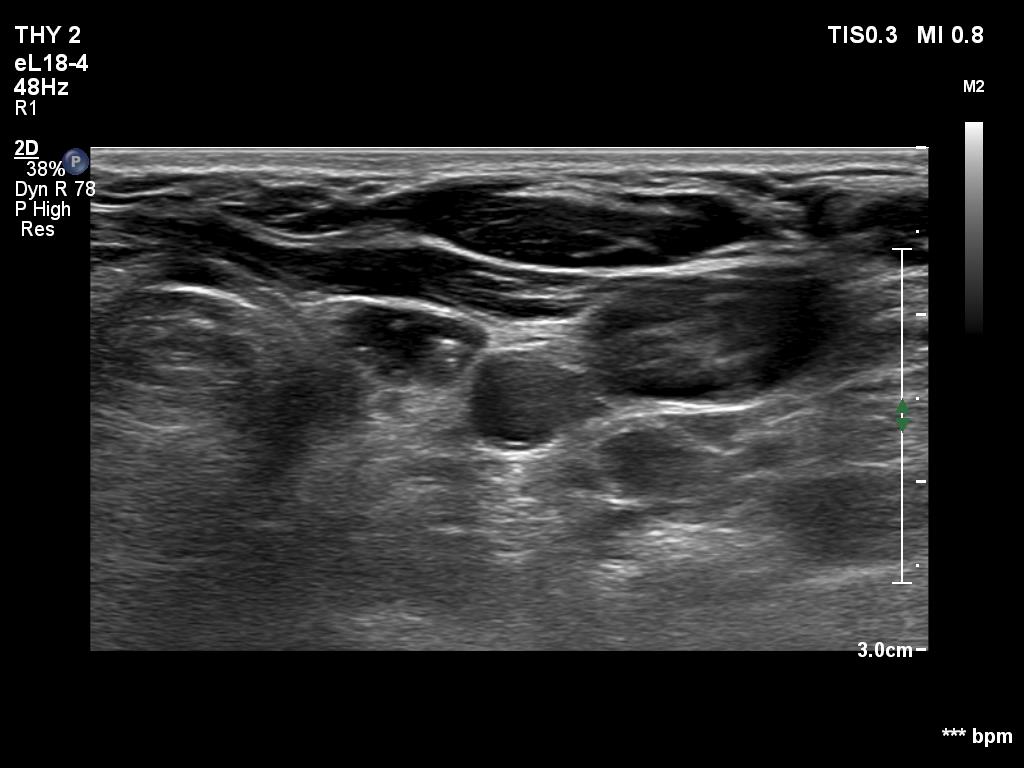

Ultrasonography. The right lobe was replaced with connective tissue. A hypoechoic mass was found in the left thyroid bed. On certain sections, this mass was very similar to a muscle fiber, however some other sections proved the presence of intralesional echogenic figures; the presence of back wall cystic figures was obvious but in the event of some granules microcalcifications should be considered. The lesion was vascularized, which excluded that the mass is muscle fiber.